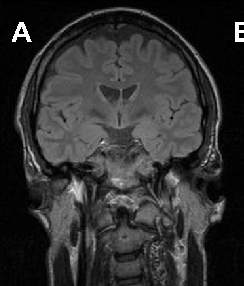

In ChAc and MLS, electroneurography may demonstrate sensorimotor axonal neuropathy whereas electromyography may show neurogenic as well as myopathic alterations. Electroencephalographic findings are not specific and may comprise normal findings, generalized slowing, focal slowing, and epileptiform discharges. Neuroradiologically, there is progressive striatal atrophy especially affecting the head of caudate nucleus and impaired striatal glucose metabolism similar to that seen in HD (Figure 2) [24,26]. Voxel-based morphometry of MRI scans in ChAc shows specific involvement of the head of the caudate nucleus [41,42]. Neurodegeneration in both core NA syndromes affects predominantly the caudate nucleus, putamen and globus pallidus. In ChAc, thalamus and substantia nigra are also involved. In contrast to HD, there is no significant cortical pathology [8,43-45]. Neuropathological findings consist of neuronal loss and gliosis of variable degree in these regions, but no inclusion bodies of any nature or other distinct neuropathological features have as yet been detected.

Cerebral MRI is often diagnostic in PKAN, and the diagnosis is confirmed by analysis of the PANK2 gene (Figure 2). Analysis of the JPH3 gene CTG expansion is useful in patients of African ancestry with suspected HDL2.

A B

C D

E F

G H

Figure 2 Neuroimaging. ChAc. Coronal FLAIR- (A) and axial T1-weighted (B) images demonstrate moderate atrophy of the caudate nucleus. MLS. Axial T2-weighted images demonstrate moderate atrophy of caudate nucleus and putamen (C) but no relevant cortical atrophy (D). HDL2. Axial FLAIR- (E) and coronal T1-weighted images (F) demonstrate atrophy of the caudate nucleus and the fronto-temporal cortex. In addition, FLAIR images show periventricular white matter hyperintensities (courtesy of Nora Chan, MD, UCLA, Los Angeles, USA). PKAN. T2-weighted fast spin echo (G) and T1-weighted (H) brain MRI scans from a child with PKAN demonstrating the “eye of the tiger” sign (courtesy of Susan J. Hayflick, MD, Oregon Health and Science University, Portland, Oregon, USA)